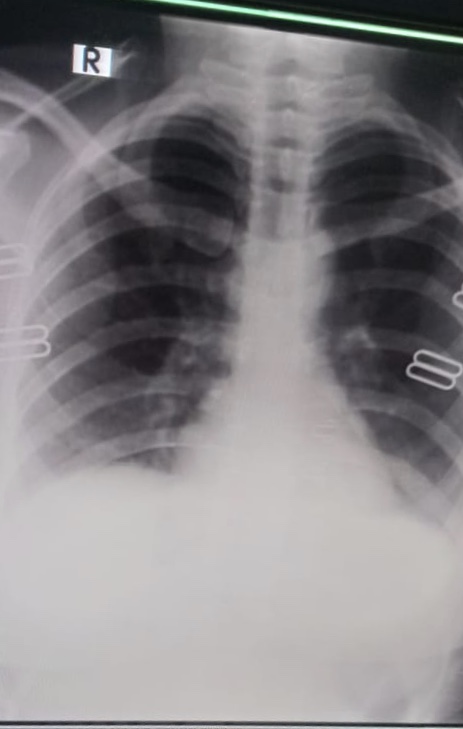

My brother is covid positive. He is diabetic too. He is having sore throat and body ache now. The attached photo is his chest X-ray. Can you please tell what’s his state now.

Chest d rat show inflamation in lungs consult online for detailed assessment